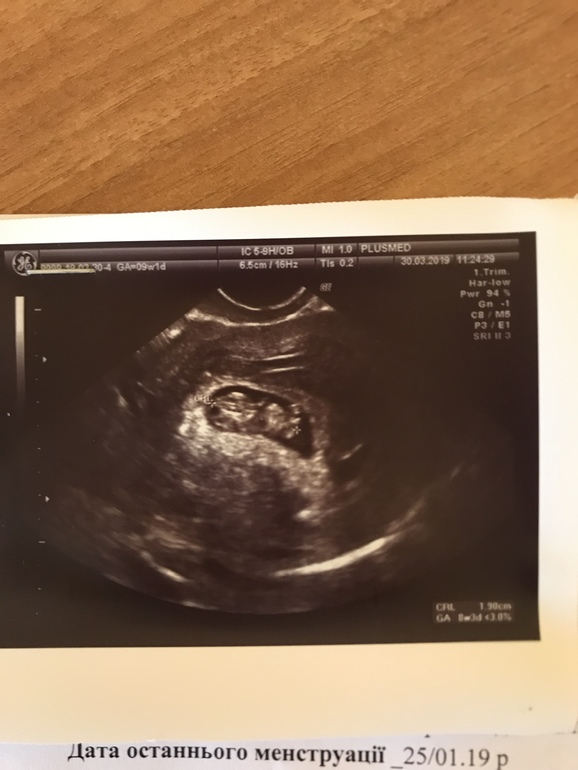

Анализы и процедуры. Помощь в расшифровке результатовЗдравствуйте, девочки. Приболела немного, температура 37,6, насморк, кашель.Была сегодня на УЗИ, срок по месячных 9 недель 1 день, по УЗИ 8 недель 3 дня. КТР 19 мм, ЧСС 167, ПЯ 28 мм, ЖМ 4 мм, толщина хориона 6 мм, ШМ 36 мм. Локализация хориона-задняя стенка матки. Ручки, ножки красиво видно.На передней стенке матки гематома до 5 мм, не связаная с плодом. По анализам крови всё в норме, кроме фибриногена-он 4,3 (норма 2-4), АЧТВ -29,9 ( норма 30-40) и ферритин 34,6 (норма 5-148), по этим вопросам в понедельник иду к гемостазиологу. Скажите, пожалуйста, всё ли нормально по УЗИ? Не большое ли отставание в развитии? Фото УЗИ добавляю.